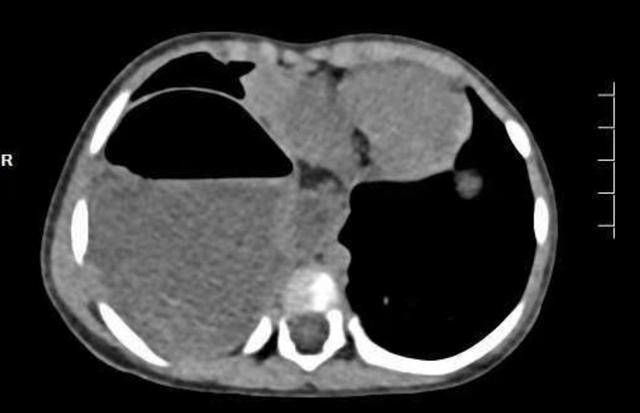

这一个多月来,1岁2个月的依依每次吃奶后都会呕吐、腹泻,反反复复不见好。焦急的家人带她到当地医院就诊,为了查清病因,医生为她安排了腹部CT检查。结果却出乎所有人的意料——依依的胃,竟然不在它应该在的腹腔里,而是穿过分隔胸腔和腹腔的肌肉层,“跑”进了右侧胸腔。

正常情况下,食管穿过膈肌进入腹腔的那个通道,在依依身上变得异常宽大,以至于胃,甚至部分结肠都从这个缺口挤进了胸腔。这不仅导致她吃进去的食物无法正常消化吸收,引起呕吐和营养不良,更严重的是,移位的内脏还压迫了她的右肺,导致肺叶无法充分张开,甚至引发了肺部感染。

(▲术前)

术中,医生清晰地看到,除了胃,还有一部分结肠也经扩大的裂孔钻进了右侧胸腔。他们精准地将这些脏器一一归位,关闭了那道异常宽大的食管裂孔,并巧妙地用胃底折叠重建了一个抗反流的“阀门”,从根源上解决了依依胃食管反流的问题。